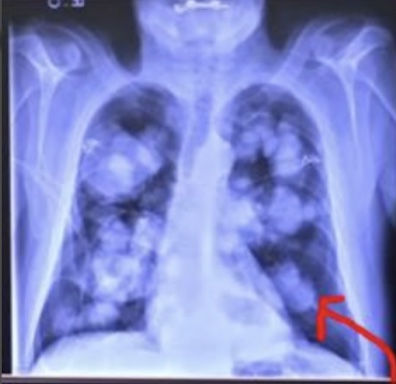

In this series, medical scans—MRI images, X-rays, and other diagnostic views—are transformed into intimate portraits that merge the clinical with the deeply personal. Each work intertwines medical imagery with biographical details, creating a layered visual narrative that honors both the physical realities of illness and the inner lives of those who endure them.

The exhibition features representations of conditions such as multiple sclerosis, lung cancer, hip and knee replacements, a broken wrist, miscarriage, and heartache—each one a story of endurance, adaptation, and faith. The artist wishes to express her gratitude to the patients and their families who entrusted her with creating artworks as unique and special as they are while acknowledging that recovery is never an individual journey; it extends to loved ones who must also heal, grieve, and rediscover vitality in the face of loss or uncertainty.

Mixed media pieces of art derived from the combination of medical scans, surveys from family and friends and genuine creativity from the creator, these artworks are one of a kind.